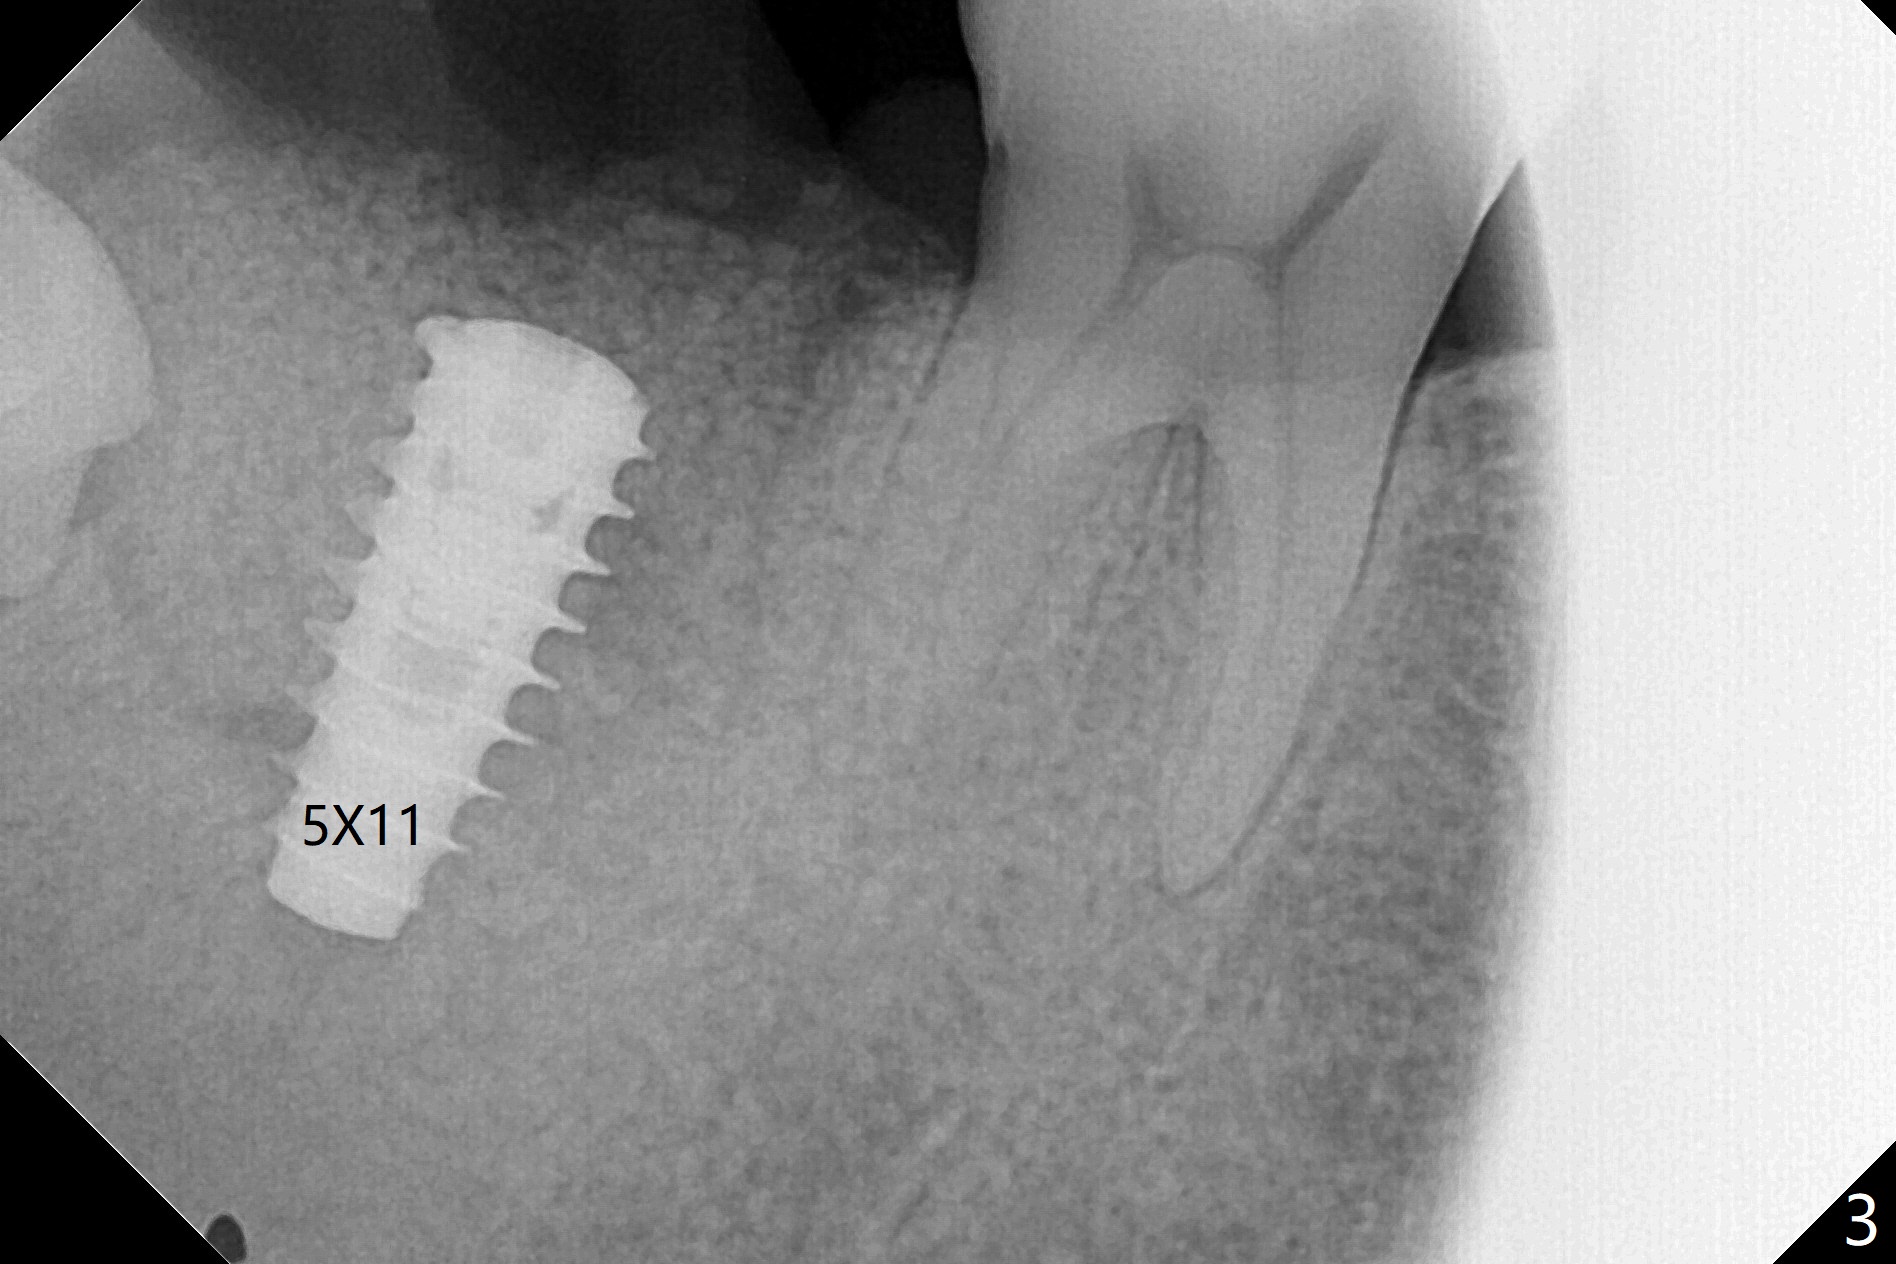

31号牙拔除前近中颊侧有一个瘘道(图一:<),说明32号牙被感染可能性小。术中发现虽然一小部分智齿牙冠与第二磨牙巨大牙槽窝相通(图二:*),但是病变并没有往智齿周围发展(S(可能是牙囊));借助导板(9毫米offset)毫无困难完成钻洞,但是嫌钻洞深度不够。由于植体扭力低(<10 Ncm),只好放置粘性骨粉(图三),覆盖PRF和Cytoplast,PTFE缝线,以及树脂敷料。病人左下第二磨牙缺失多年,牙槽嵴粘膜出现白色病变(图四:箭头),可能与对合磨牙延申有关(图五:箭头)。如果这个牙位需要导板植牙,垂直距离将是一个严峻问题。即种导板(图六:31)与延期导板(18)金属圈放置有不同,相差1.5毫米(图七):即种(由于拔牙)金属圈可以放低,而愈合牙位(由于牙龈存在)金属圈必须放高。所以第二磨牙即种有足够垂直空间优势。术后一周复诊,老的树脂敷料不牢(因为下面没有基台),脱落,下面不可吸收膜没有外翻,重新制作敷料(图八:A)。术后一个月由于2,3号牙之间牙周炎发作,树脂敷料牢靠,下面不可吸收膜稍微暴露,两者取出后,植体略微暴露。没有基台,骨粉固定好像不佳。